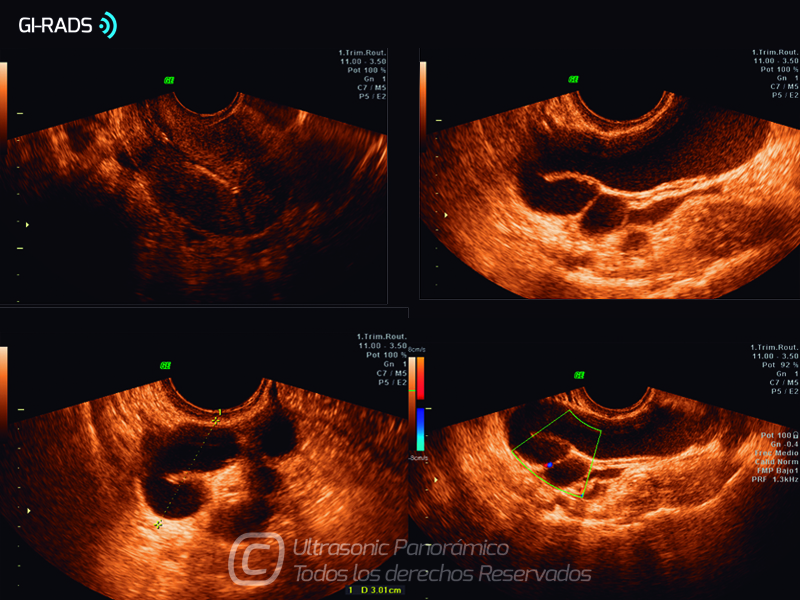

Patologías Benignas – Abceso Tubo Ovárico

• Patologías Benignas – Abceso Tubo Ovárico